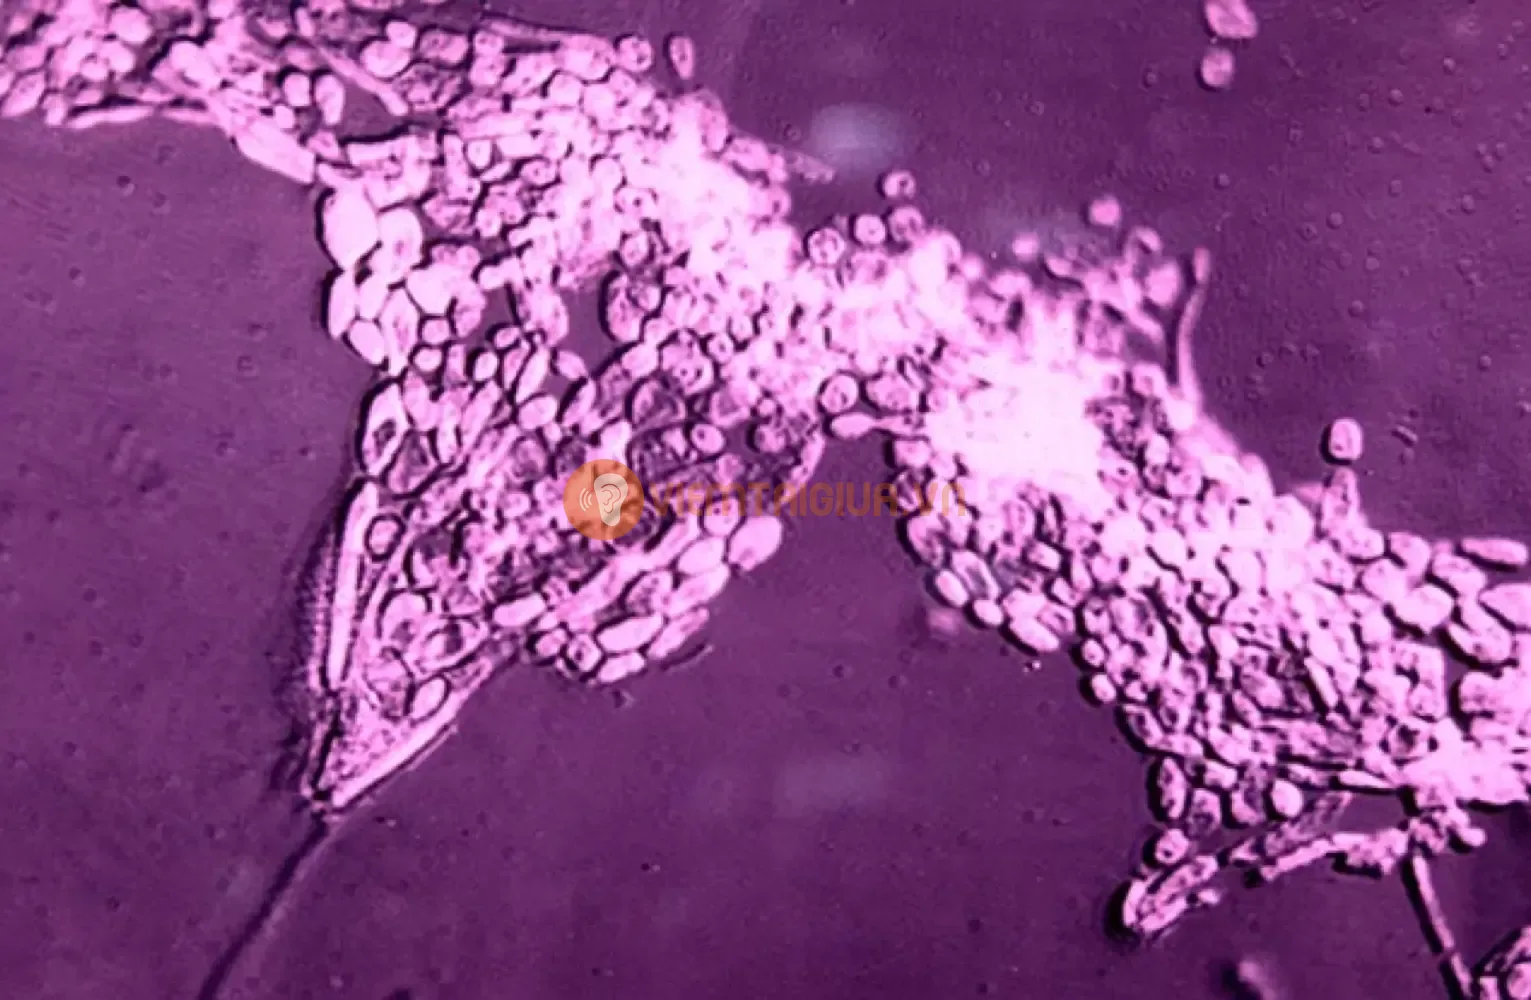

2.1. Aspergillus

2.1.1. Đặc điểm nhận diện

Aspergillus là một trong những loại nấm phổ biến nhất gây ra otomycosis. Loại nấm này có thể được tìm thấy trong môi trường tự nhiên như đất, không khí, và chất hữu cơ phân hủy. Aspergillus thường tạo thành các bào tử nhỏ và dễ dàng lây lan qua không khí, khiến nó dễ dàng xâm nhập vào tai người.